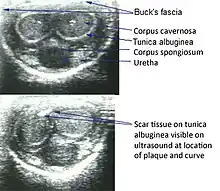

Ultrasonography

On penile ultrasonography, the typical appearance is hyperechoic focal thickening of the tunica albuginea. Due to associated calcifications, the imaging of patients with Peyronie's disease shows acoustic shadowing, as illustrated in figures below. Less common findings, attributed to earlier stages of the disease (still mild fibrosis), are hypoechoic lesions with focal thickening of the paracavernous tissues, echoic focal thickening of the tunica without posterior acoustic shadowing, retractile isoechoic lesions with posterior attenuation of the beam, and focal loss of the continuity of the tunica albuginea.

In the Doppler study, increased flow around the plaques can suggest inflammatory activity and the absence of flow can suggest disease stability. Ultrasound is useful for the identification of lesions and to determine their relationship with the neurovascular bundle. Individuals with Peyronie's disease can present with erectile dysfunction, often related to venous leakage, due to insufficient drainage at the site of the plaque. Although plaques are more common on the dorsum of the penis, they can also be seen on the ventral face, lateral face, or septum.[13]